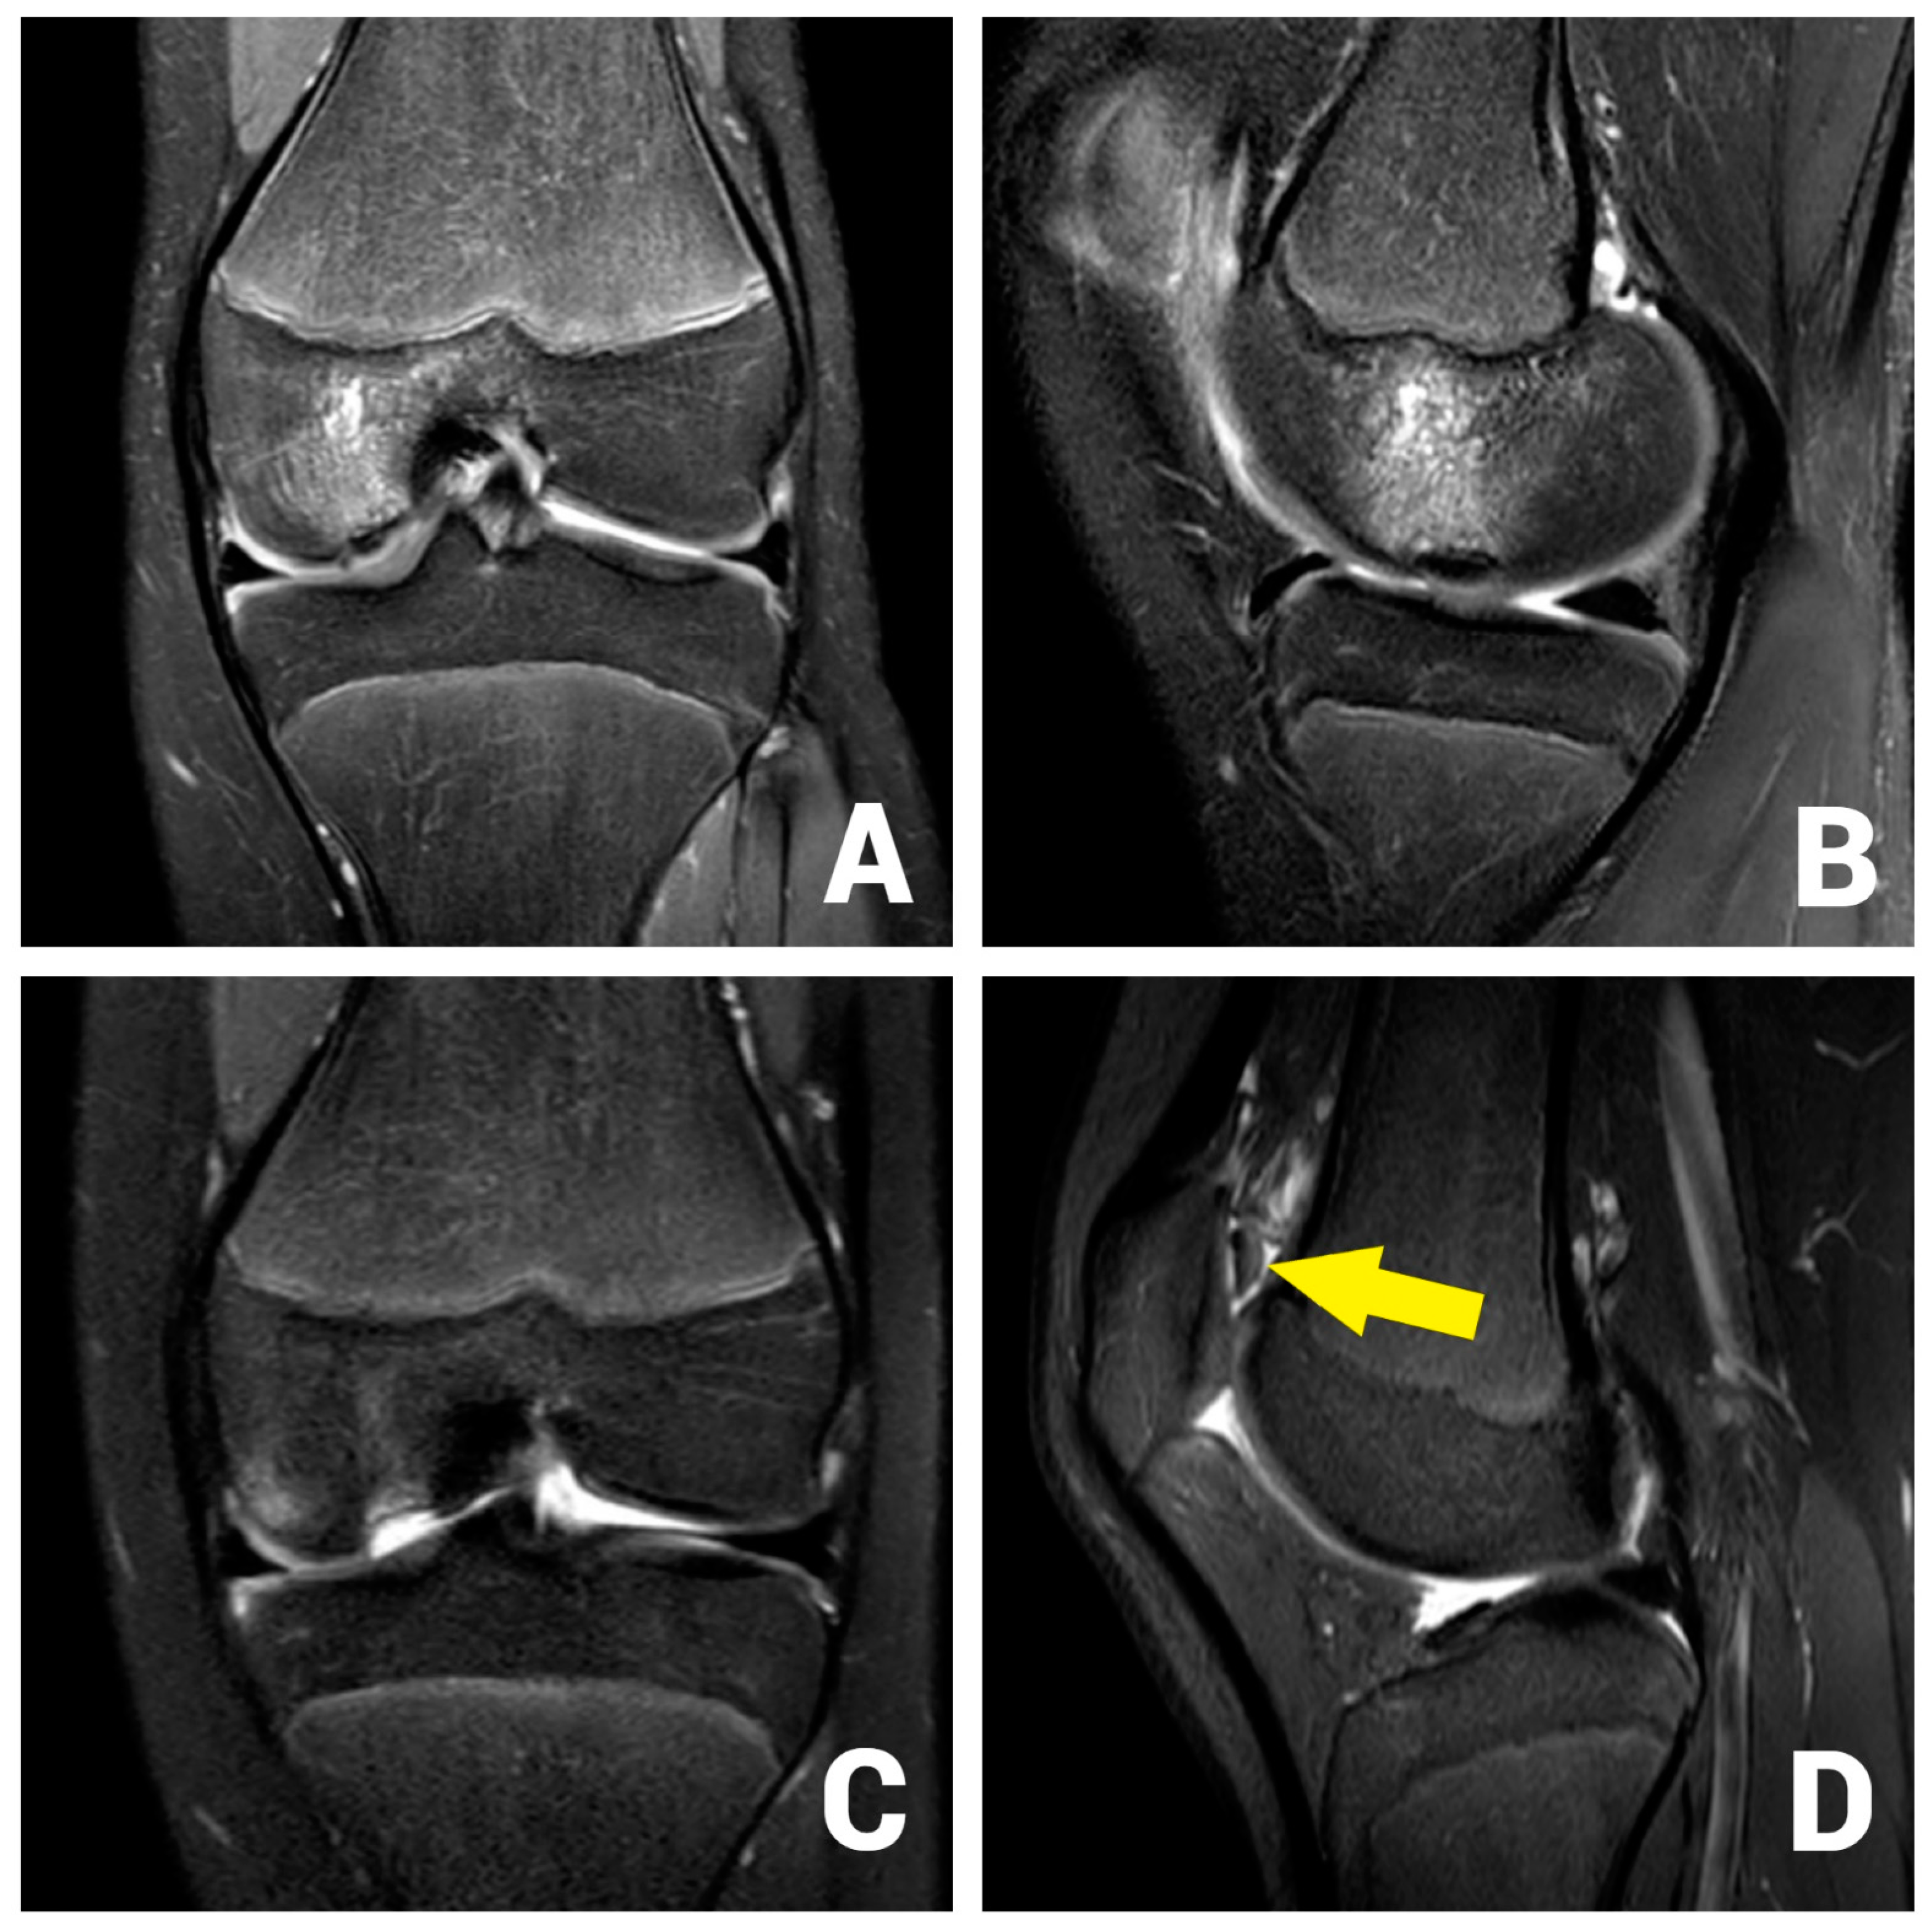

2. Case Report